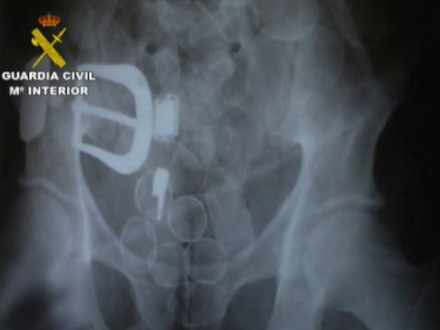

Ifølge rapporten fra Guardia Civil blev offeret, J.A.U.I., en colombiansk advokat med spansk pas, hyret af narkobagmanden fra sit hjemland til at transportere kokain i maven fra Sydamerika til Spanien.

Lige efter ankomsten til Spanien fik manden forfærdelige mavesmerter og bad sin 'arbejdsgiver', den colombianske narkobagmand J.A.V.H, om at komme på sygehus. Alt tydede på, at der var gået hul på en af pakkerne i hans mave og at han hurtigt blev forgiftet indefra. Han havde akut brug for hjælp.

Men det afviste narkobossen, der var mere bange for at miste narkoen. Han gav i stedet sit muldyr en ordentlig dosis smertestillende medicin for at milde den ulidelige smerte.

Retsmedicinere har efterfølgende slået fast, at manden døde af forgiftning, og fik skåret maven op post mortem. Narkoen var herefter blevet taget ud, og maven var igen blevet syet sammen med fiskesnor.